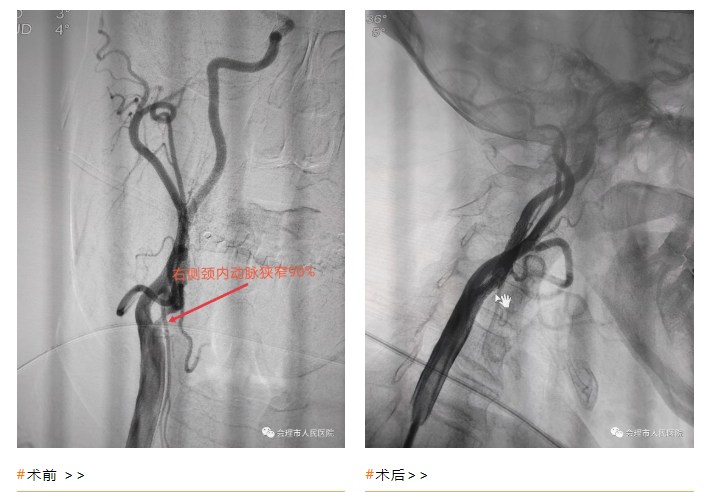

3月12日,在自贡市第三人民医院神经内科王力主任指导下,介入团队为第100位患者实施脑血管造影术,术中发现右侧颈内动脉起始部和左锁骨下动脉血管狭窄程度约90%,该患者具备实施右侧颈内动脉远端血管保护装置植入术+右侧颈内动脉球囊扩张成形术+右侧颈动脉支架植入术+左锁骨下动脉支架植入术的手术指征。但该手术难度大,风险高,为了防止球囊扩张过程中栓子脱落,避免术中发生向远端血管“逃逸”导致血管栓塞,介入导管室邓加华副主任医师先将保护伞植入到远端血管狭窄处,然后小心翼翼用球囊将其狭窄的血管进行充分扩张,精准的将颈动脉自膨式支架植入病变血管处,同时回收保护伞撤出体外,打通了患者大脑供血的“主干道”,整个手术非常顺利,规避了术中血栓栓塞事件,手术效果好,得到了患者及家属的高度评价。